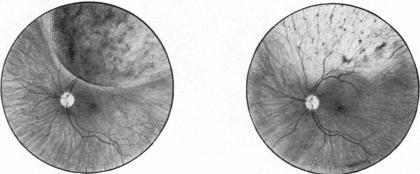

Radiotherapy for malignant melanoma of the choroid.

Br J Ophthalmol. 1966 Mar;50(3):147-55. doi: 10.1136/bjo.50.3.147.